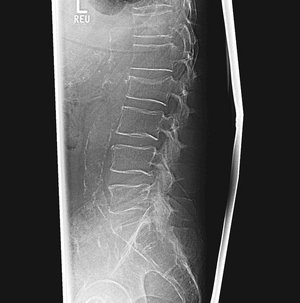

MRT-Aufnahme der Lendenwirbelsäule, zeigt Bandscheiben und Wirbelkörper.

Bei einer akuten lumboischialgiformen (ins Bein ausstrahlenden) und dermatombezogenen Klinik mit möglichen neurologischen Störungen (motorisch und sensorisch) sowie einem chronifiziertem Schmerzsyndrom bei entsprechend radiologisch gesichertem Bandscheibenvorfall steht die Indikation zur Mikrodiskektomie desselben.

In unserer Klinik wird eine offene mikrochirurgische Operation unter Zuhilfenahme eines Operationsmikroskopes als Standardverfahren gewählt. Eine spezielle perioperative Lagerung zur Minimierung der Operationsrisiken wird umgesetzt.